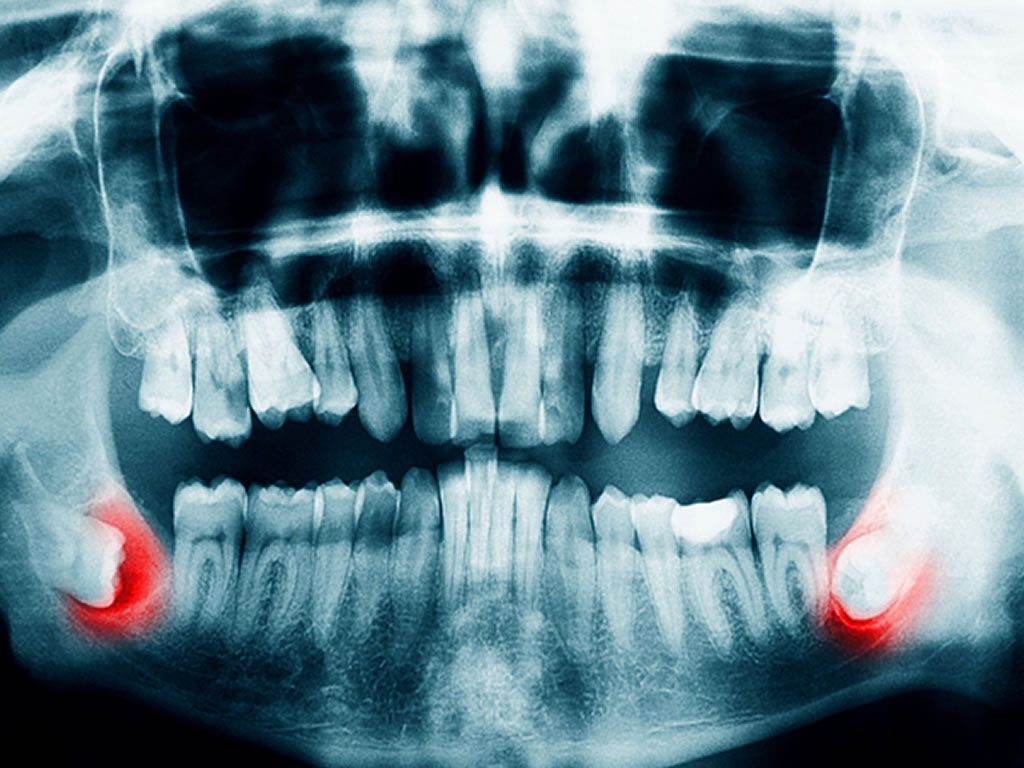

Wisdom Tooth Extraction

Wisdom teeth are a common candidate for removal as they are often a source of problems. Issues such as improper eruption and impaction (being stuck) often cause infection and pain.

Other issues may include difficulty of cleaning, causing cavities and gum disease.